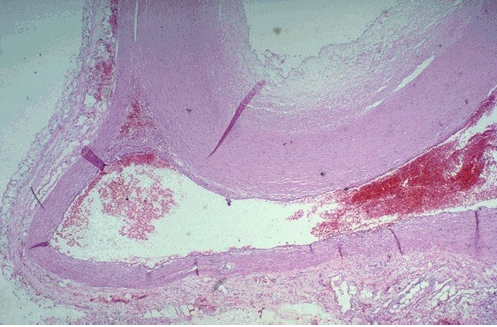

- A cross section through the heart reveals a ventricular aneurysm with a very thin wall at the arrow

- Note how the aneurysm bulges out

- The stasis in this aneurysm allows mural thrombus, which is present here, to form within the aneurysm